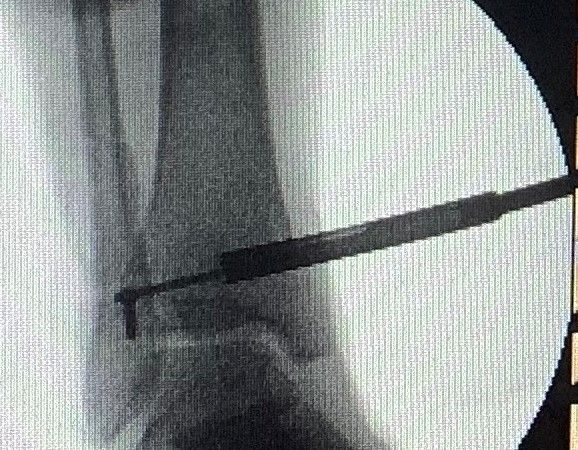

4. Metal work in lateral malleolus with the syndesmotic screw to be broken in a 30-year-old male.

Treatment: Removal all the implant work plus the syndesmotic screw with specific technique.

The lag screw did not remove I. Ten months down the line of the procedure, anteroposterior x-ray ankle shows the broken screw II. During the procedure a specific technique is using to remove the major part of the broken screw III. Anteroposterior view during the procedure is showing that the broken screw has been removed